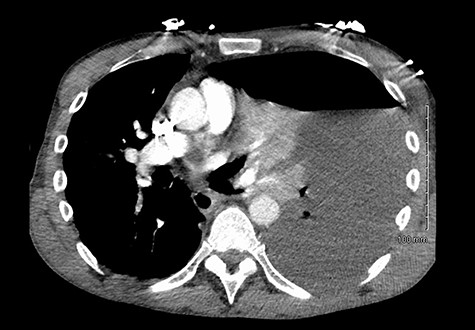

He was readmitted three days post-discharge with worsening pleuritic chest pain and dyspnoea. On admission, he was febrile and tachycardic. On examination, he had absent breath sounds and dullness to percussion over the left mid and lower zones of his chest. Chest x-ray confirmed a large left-sided pleural effusion (Fig. 1), which was consistent with a massive haemopneumothorax on cross-sectional imaging (CT) (Fig. 2). A chest drain was inserted that drained 6 l of serosanguinous fluid. The patient deteriorated thereafter and required inotropic support and empirical broad-spectrum antimicrobials, piperacillin-tazobactam (4.5 g IV) and gentamicin (5 mg/kg IV) in the intensive care unit.